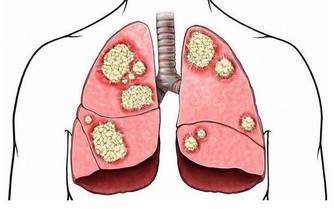

健康人呼吸平穩、規律,每分鐘15次左右,

如發現呼吸的深度、頻率、節律異常,呼吸費力、有胸悶、憋氣感受,則為不正常表現,應就醫。

呼吸增快主要見於肺炎、肺栓塞、胸膜炎、支氣管哮喘、充血性心力衰竭、代謝亢進以及神經精神障礙等。